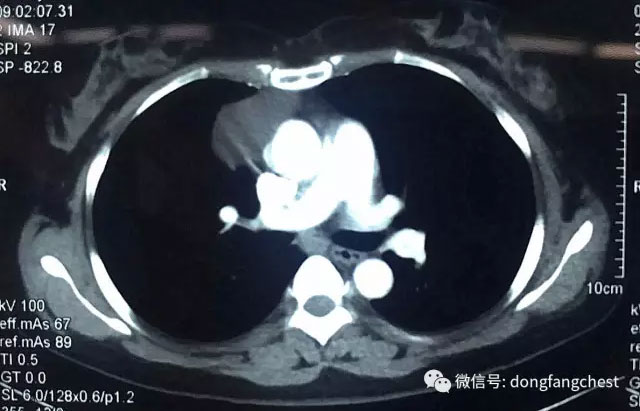

淮南市本地患者张女士今年57岁,2年前体检时发现前纵隔肿物,自从发现胸腔内的长了肿物后,张女士倍感压力,经常觉得各种不适。今年4月,张女士入院再次复查CT发现,胸腔内肿物较之前明显增大,这更让张女士和她的家人十分担心,甚至寝食难安。

经多家医院就诊咨询后,张女士选择入住东方总院胸外科进行治疗。经过术前详细的检查和针对张女士“糖尿病、高血压病”的调整准备后,以朱胜、王鸿主任为首的胸心外科团队为张女士安排了“单孔胸腔镜纵隔肿物切除”手术。为最大程度减少患者的损伤以及切口的美观,主刀医师王鸿主任仅在2cm长的小切口下就成功完整切除了约6cm大小的纵隔肿瘤,手术过程仅耗时半个多小时,手术几乎没有出血。

据东方医院集团总院胸心外科王鸿主任介绍,张女士的纵隔肿瘤贴在纵隔大血管旁边生长,手术切除具有较大风险。传统手术治疗需要取15cm以上的大切口开胸切除肿瘤,手术创伤大,患者术后恢复慢。近10余年来,经过不断的探索、实践和发展,胸腔镜微创手术技术已经成为胸外科疾病的主要治疗手段。单孔胸腔镜手术技术是胸腔镜微创手术技术进一步发展的产物,目前已广泛应用于胸外科疾病的诊治:如胸外伤、气胸、胸膜及纵隔淋巴结的活检、肺局部切除、肺叶切除、肺段切除、纵隔肿瘤切除等。与传统胸腔镜手术技术相比,单孔胸腔镜手术切口设计取消了腋后线切口及腋中线观察孔切口,所有操作器械包括胸腔镜镜体均由一个3~5cm长的切口内进出,因此损伤更小,该切口选择部位为胸壁肌肉最薄弱的位置,术后疼痛更轻,对患者感觉和运动影响也更小。由于切口选择在相对隐匿的部位,如腋窝和乳房下缘,从而使得切口更加美观,也改善了手术对患者生理及心理上的影响。在应用过程中发现,对于心肺功能相对差的患者,单孔胸腔镜手术也可以降低手术的风险。